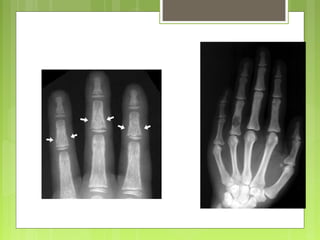

Condroma - Los solitariosse localizan en la región metafisaria de los huesos cilíndricos, sobre todo en manos y pies. - Los múltiples (encondromatosis) se conocen como enfermedad de Ollier o síndrome de Maffucci (si se asocia a angiomas de partes blandas).

• Tumores decartílago más frecuentes y se suelen diagnosticar entre los 20-50 años. • Pueden originarse en la cavidad medular (encondromas) o en la superficie del hueso (condromas subperiósticos o yuxtacorticales). • Los encondromas pueden ser solitarios o múltiples. Condroma

Condromas

Mano